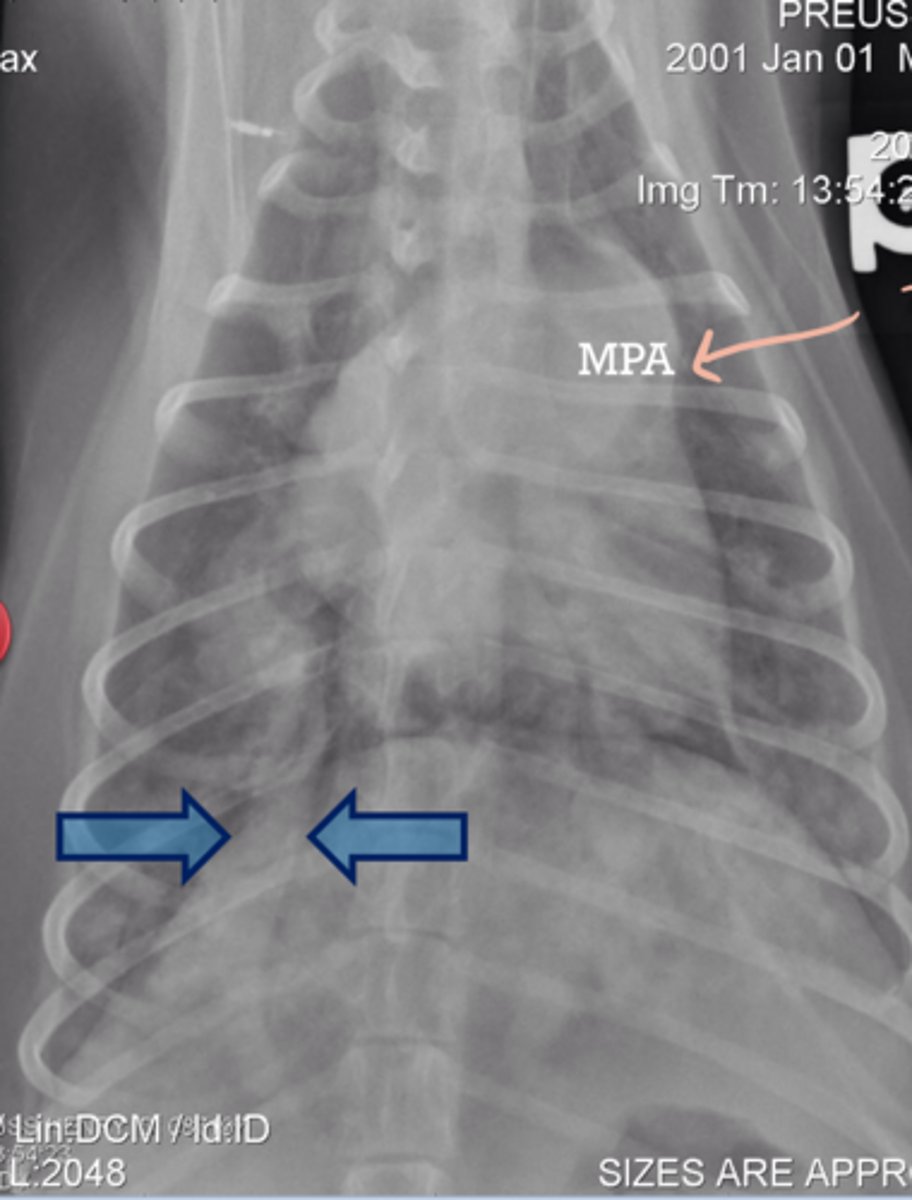

Heart - 13.5VHS

L atrial enlargement

Dilated pulmonary A. and V.

Given the radiograph which structures are enlarged?